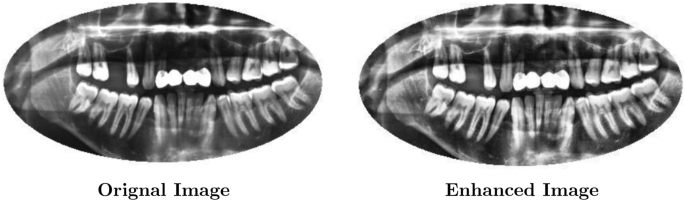

AHE is a useful preprocessing technique in the proposed framework for dental radiographs. It adjusts the local contrast based on mathematical transformations of the pixel intensity distribution to highlight the details essential for diagnosing dental diseases. AHE improves contrast in particular image areas without over-amplifying noise in other areas. Figure 3 indicates an example of images after applying this technique.